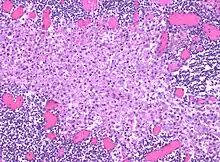

Histiocytosis is a group of disorders that result in excessive number of histiocytes (dendritic cells or monocyte macrophages).[1][3] Symptoms are variable.[2] Commonly affected organs include skin, bone, lungs, lymph nodes, nervous system, and heart.[2]

The underlying mechanism may involved genetic changes in the mitogen-activated protein (MAP) kinase cell-signaling pathway.[2] Diagnosis is based on tissue biopsy, symptoms, and medical imaging.[2] Types include Langerhans cell histiocytosis (LCH), juvenile xanthogranuloma, Erdheim-Chester disease, hemophagocytic syndrome, and Rosai-Dorfman disease.[1]